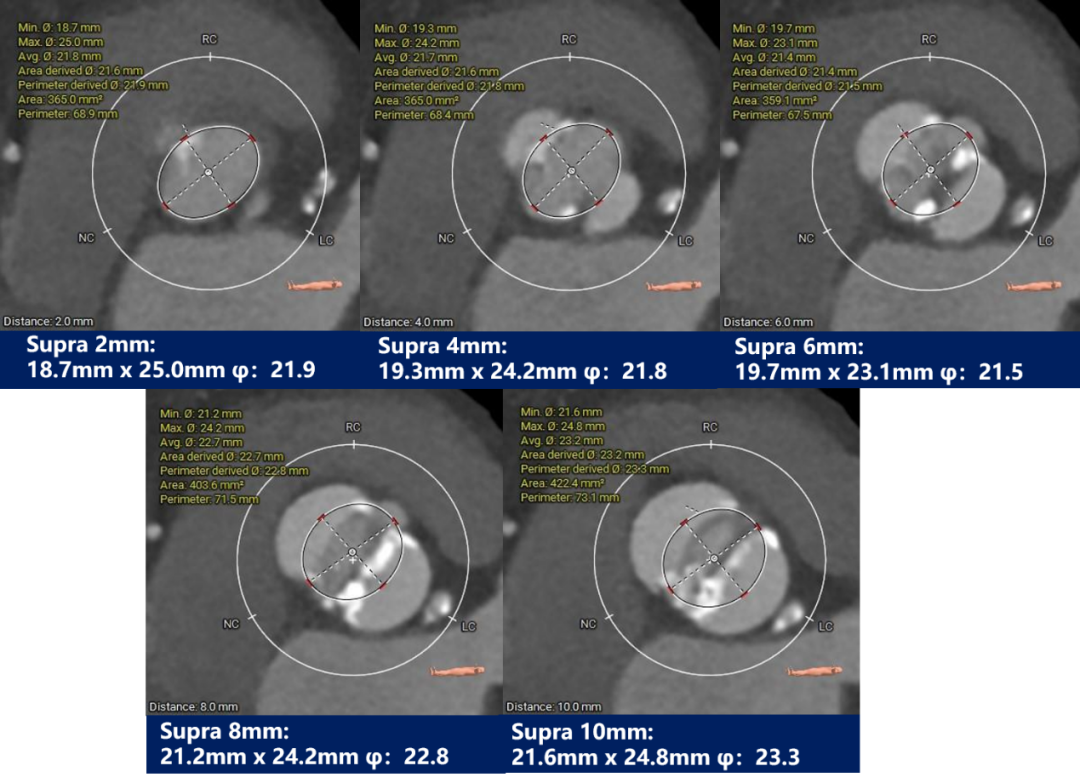

瓣上测量

瓣上测量:瓣叶重度钙化伴增生肥厚,钙化分布不均,主要分布于瓣叶边缘及后壁交界附着缘。

3. 依据瓣环及瓣上测量结果,行20mm球囊预扩张,预装AV23瓣膜;